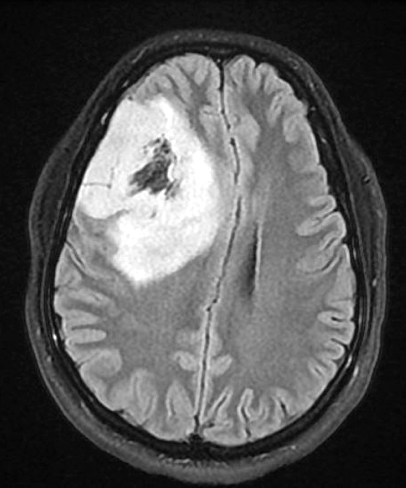

Radiology description

- Computed topography (CT):

- Mixed density (hypodense and isodense) located in cortex or subcortical white matter (Radiology 2017;284:316)

- High attenuation areas, likely from calcifications

- MRI:

- Heterogeneous on T1 and T2 weighted imaging

- Typically no diffusion restriction

- Poorly circumscribed borders (AJNR Am J Neuroradiol 2017;38:678)

- Cystic changes are relatively common (Radiology 2017;284:316)

- Contrast enhancement present in < 20% of WHO grade 2 tumors and > 70% of WHO grade 3 tumors (AJNR Am J Neuroradiol 2012;33:852, Eur J Cancer 2019;107:15)

- Elevated 2HG by magnetic resonance spectroscopy could serve as radiologic surrogate of IDH mutation status (Nat Med 2012;18:624)

Radiology images